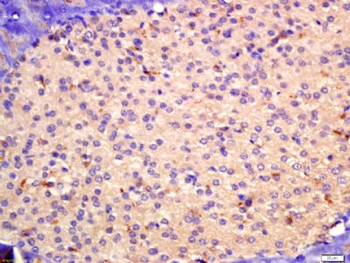

50 μl, 100 μl, 200 μlAnti-Aurora A/AURKA Antibody [orb1290027]

ELISA, FC, IHC, WB

Human

Rabbit

Polyclonal

Unconjugated

10 μg, 100 μgChemerin Rabbit Polyclonal Antibody [orb156351]